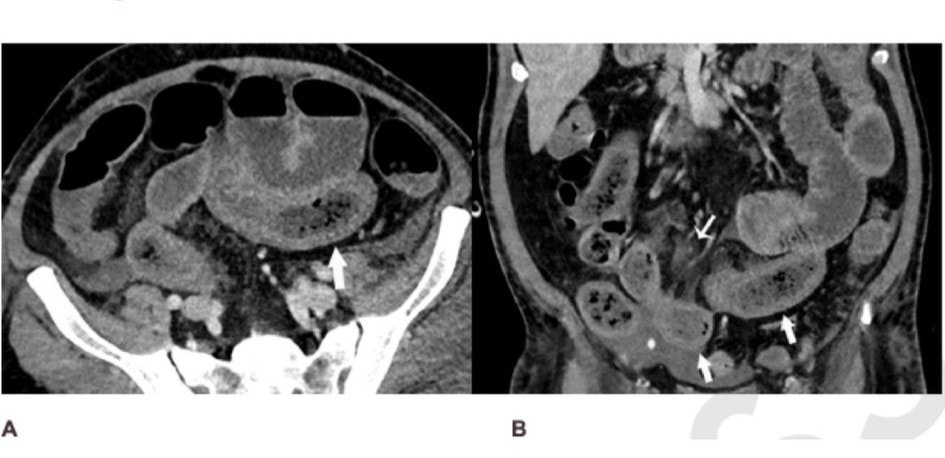

Una tomografía computarizada del abdomen y la pelvis de un hombre de 57 años sospechoso de tener un suministro de sangre deficiente en el intestino. La exploración muestra que su intestino delgado estaba distendido y engrosado en partes. Foto: Radiological Society of North America

Los hallazgos, publicados en la revista Radiology, mostraron signos de anomalías y problemas intestinales, y el flujo de bilis fue común en los escaneos de los pacientes. Alrededor de 31 por cientos de los escaneos mediante tomografías computarizadas mostraron que los pacientes tenían problemas en la pared intestinal.

También se encontró que los pacientes tenían padecimientos como el engrosamiento de la pared intestinal, así como quistes de gas en dicha pared y en la vena que lleva la sangre del tracto gastrointestinal y del bazo hacia el hígado. Uno de los pacientes presentaba una perforación intestinal. En 20 por ciento de los pacientes en cuidados intensivos, había signos de que el suministro de sangre a los intestinos era inadecuado.

“Algunos de los síntomas son típicos de la isquemia intestinal o necrosis del intestino, y en las personas sometidas a cirugía pudimos ver pequeños trombos vasculares junto a las áreas de necrosis intestinal.